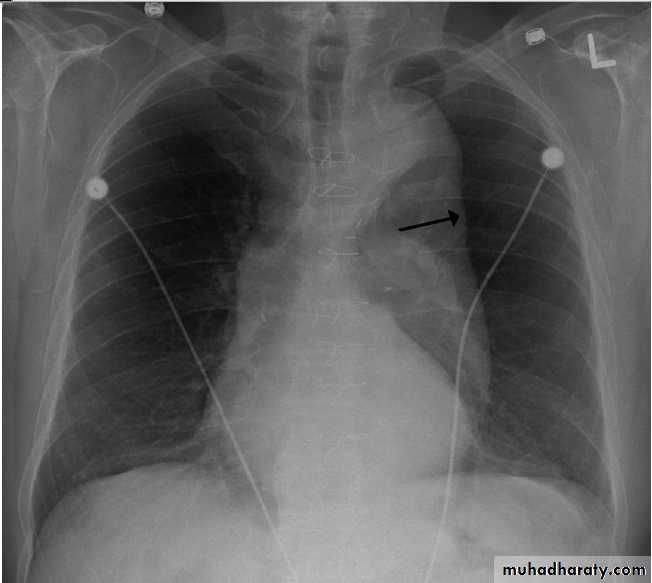

Pleural Effusion on Chest Radiographs.

Posteroanterior (A) and lateral (B) chest radiographs demonstrate the typical meniscoid appearance (arrows) in a patient with a left pleural effusion

Hydropneumothorax.

When fluid and air are present in the pleural space on an upright chest x-ray, a perfectly straight horizontal line will extend all the way from the spine to the edge of the pleural cavity. In this patient, a loculated right basilar hydropneumothorax is present.

The air/fluid interface is easily seen (arrows). If this were a lung abscess, the air/fluid level would be very unlikely to extend all the way from the medial to the lateral aspect of the hemithorax.